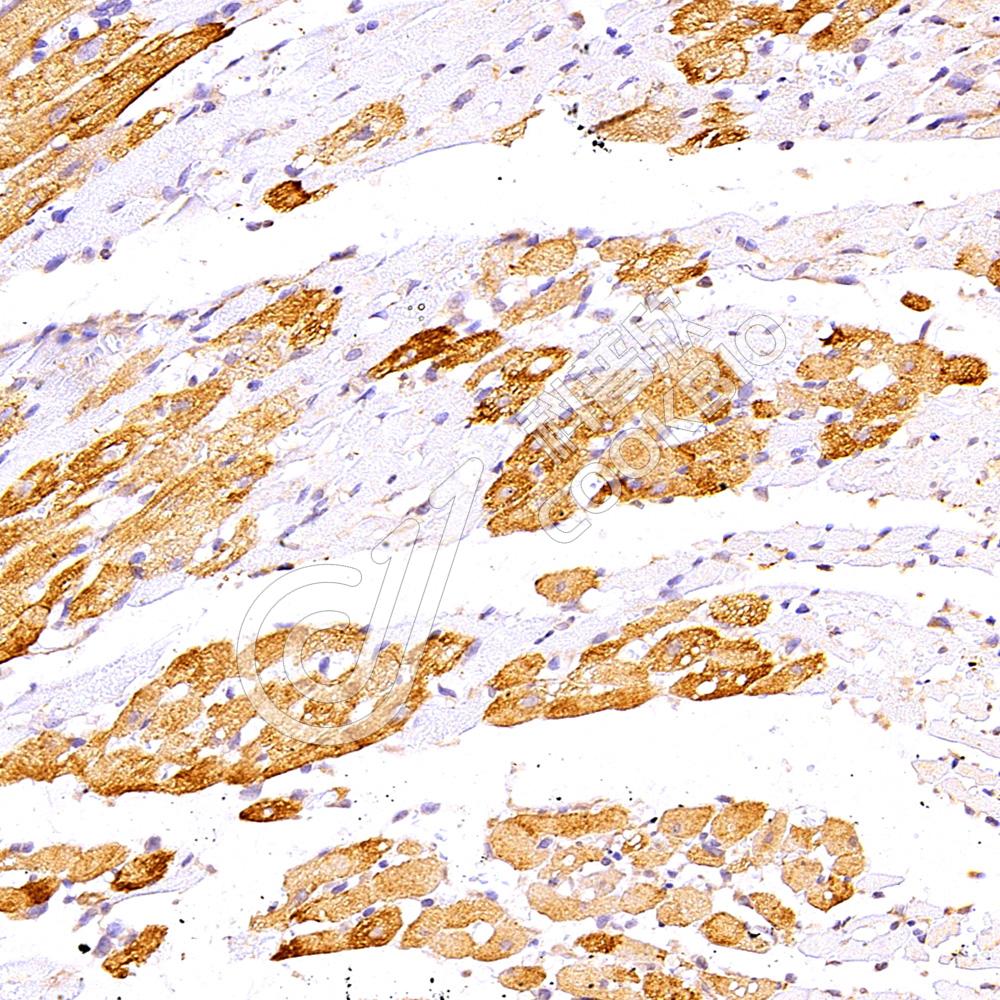

IHC检测Cardiac Troponin I蛋白(货号 K1337224).

样品: 大鼠心脏缺血再灌注损伤, 4%多聚甲醛 (货号KSG1101) 固定12-24小时.

抗原修复: 柠檬酸抗原修复液(干粉, pH 6.0) (KSG1201), 98℃, 20分钟.

—抗: 1: 300稀释, 4℃ 孵育过夜.

二抗: S-vision免疫组化多聚二抗(山羊抗兔),即用型 (货号KB3906), 室温孵育20分钟.